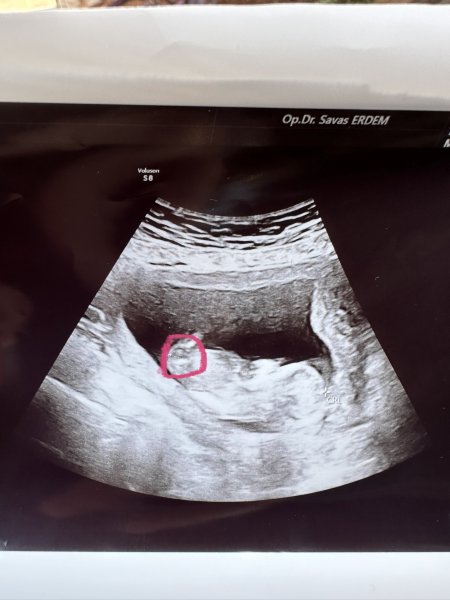

Hayatım resim tam görünmüyor da ne istiyorsun sen bu resim sonucuna göre cinsiyet tahmini mi istiyorsun ?

Hayatım elinde başka resim var mı NUB a göre cinsiyet tahmini yapmak isterim ama bu resim malesef yetersiz baya parlamış görünmüyor apış bölümü :D:D